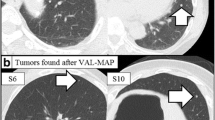

Intraoperative localization procedures

Immediately after injecting methylene blue, the skin was disinfected and thoracoscopy was performed to locate the stain. The surrounding surface was palpated using the index finger for the lesion. The wedge resection of the identified lesion was performed using VATS along with a 3 cm margin of normal lung tissue, including the stained area, and the specimen was placed next to a 5 ml syringe which was taken as a reference length scale to measure the distance between the edge of the lesion and the edge of the stain (Figure 6). The specimen was sent for immediate pathologic examination. All patients with malignant lesions subsequently underwent lobectomy and systematic lymph node dissection. For those with benign lesions, the surgery was completed.

All patients with successfully localized malignant lesions subsequently underwent lobectomy via VATS and systematic lymph node dissection. The postoperative pathology examination revealed all cancer cases as stage T1aN0M0. Wedge resection was performed to remove benign lesions. There were no complications observed in any of the patients as a result of the localization. Among five unsuccessful localized lesions, four were later localized through thorough index palpation around 20-23 mm from the stain. Only one lesion was not localized and the patient underwent thoracotomy. Since the pathologic examination confirmed as a lung cancer case, this patient underwent lobectomy by thoracotomy.